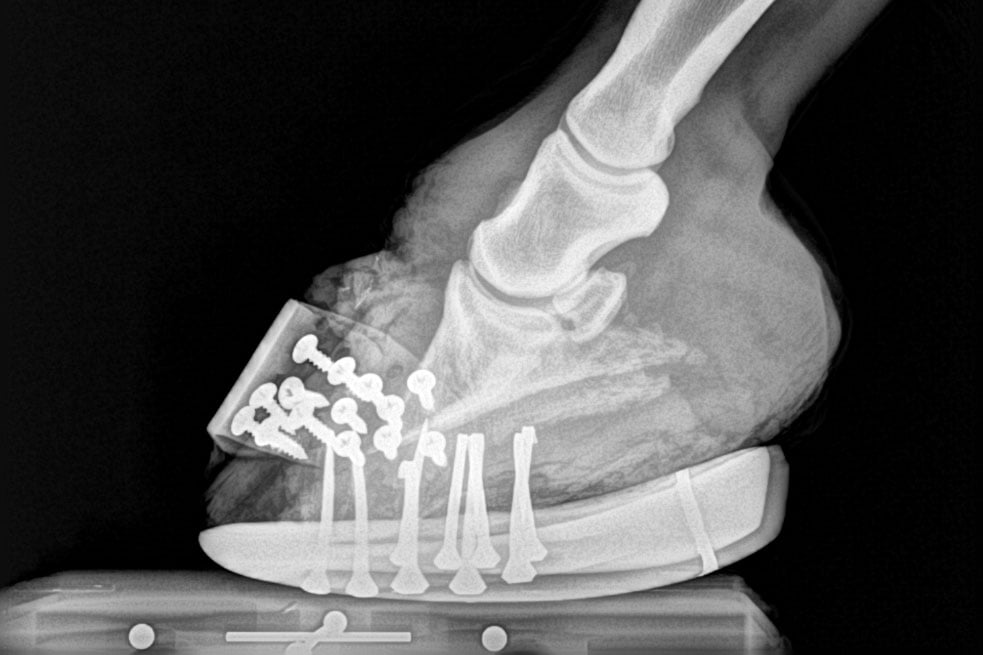

Every day veterinarians across the country see hundreds of cases of laminitis, a painful disease that affects the feet of horses. Laminitis results from the disruption of blood flow to the sensitive and insensitive laminae within the foot, which secure the coffin bone to the hoof wall.

- Dished hooves, which are the result of unequal rates of hoof growth